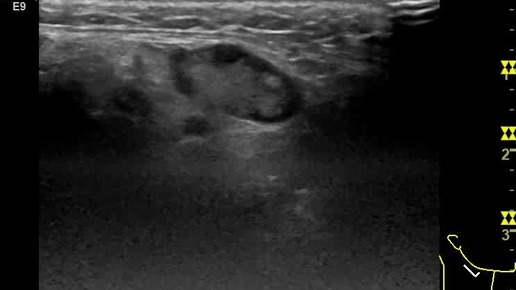

Видео к статье https://dzen.ru/a/Znp1GRgesS7Ia-wF. Опухоль слюнной железы. Лимфатический узел

Ультразвуковые находки от врача УЗД Зорина Я.П.